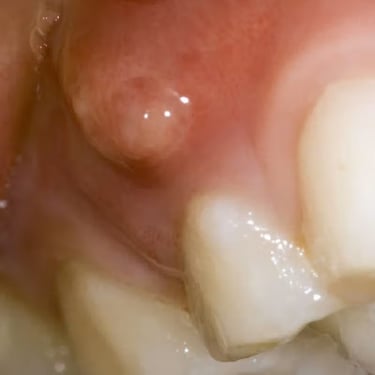

Absceso Periapical Crónico

Un absceso periapical crónico es una infección prolongada en la punta de la raíz del diente que forma una bolsa de pus.

Los pacientes pueden tener dolor leve o no tener síntomas, pero notar una fístula en la encía.

El tratamiento incluye un tratamiento de conducto y, en algunos casos, una cirugía apical. Es crucial tratarlo para evitar la propagación de la infección.